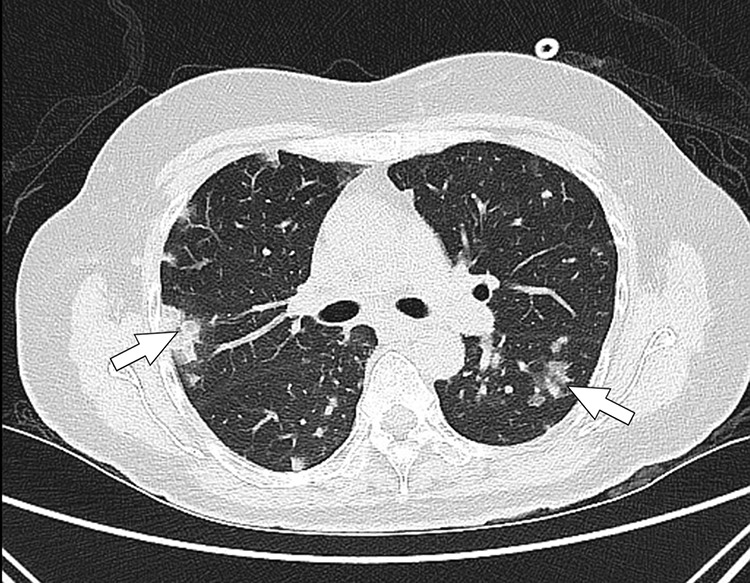

椎管旁类固醇注射,虽然广泛用于治疗背痛,但有严重并发症的风险,包括感染。我们描述了一位54岁的免疫功能正常的女性,她在腰椎棘旁类固醇注射治疗背痛后发生了弥散性耐甲氧西林金黄色葡萄球菌(MRSA)感染。患者表现为发热、呼吸困难和急性腰痛,进展为缺氧性呼吸衰竭,需要插管。诊断结果显示MRSA菌血症并发腰椎硬膜外脓肿、双侧腰肌和腰方肌化脓性炎、下腔静脉(IVC)脓毒性血栓性静脉炎、肺脓毒性栓塞和脑膜脑炎。患者接受静脉注射万古霉素和阿哌沙班抗凝治疗。在完成8周的疗程后,观察到临床改善,菌血症消退,下腔静脉血栓放射学完全消退。该病例强调了MRSA在其强大毒力因素的驱动下,将局部感染转化为广泛转移性疾病的破坏性潜力。它指出了早期识别系统性并发症的重要性,包括血管血栓形成和中枢神经系统受累,在椎管旁干预后。此外,它表明需要及时成像,及时施用靶向抗生素和多学科管理。鉴于越来越多地使用皮质类固醇注射和对抗生素耐药病原体的日益关注,该病例提醒人们注意潜在的医源性并发症以及感染控制和警惕监测的至关重要性。即使没有明显的免疫抑制,临床医生也应该对注射类固醇后出现全身性症状的患者保持高度怀疑。

Paraspinal steroid injections, while widely employed for the treatment of back pain, carry risks of serious complications including infection. We describe a 54-year-old immunocompetent woman who developed a disseminated methicillin-resistant Staphylococcus aureus (MRSA) infection following a lumbar paraspinal steroid injection for back pain. She presented with fever, dyspnea, and acute low back pain, progressing to hypoxic respiratory failure requiring intubation. Diagnostic workup revealed MRSA bacteremia complicated by a lumbar spinal epidural abscess, bilateral psoas and quadratus lumborum pyomyositis, inferior vena cava (IVC) septic thrombophlebitis, pulmonary septic emboli, and meningoencephalitis. The patient received intravenous vancomycin and anticoagulation therapy with apixaban. Clinical improvement was observed with resolution of bacteremia and complete radiological resolution of the IVC thrombus after completing an 8-week treatment course. This case underscores the devastating potential of MRSA to transform a localized infection into widespread metastatic disease, driven by its potent virulence factors. It points out the importance of early recognition of systemic complications, including vascular thrombosis and central nervous system involvement, following paraspinal interventions. Moreover, it demonstrates the need for prompt imaging, timely administration of targeted antibiotics, and multidisciplinary management. Given the increasing use of corticosteroid injections and rising concerns about antibiotic-resistant pathogens, this case serves as a reminder of potential iatrogenic complications and the critical importance of infection control and vigilant monitoring. Clinicians should maintain a high index of suspicion for deep-seated infections in patients presenting with systemic symptoms after steroid injection, even in the absence of overt immunosuppression.